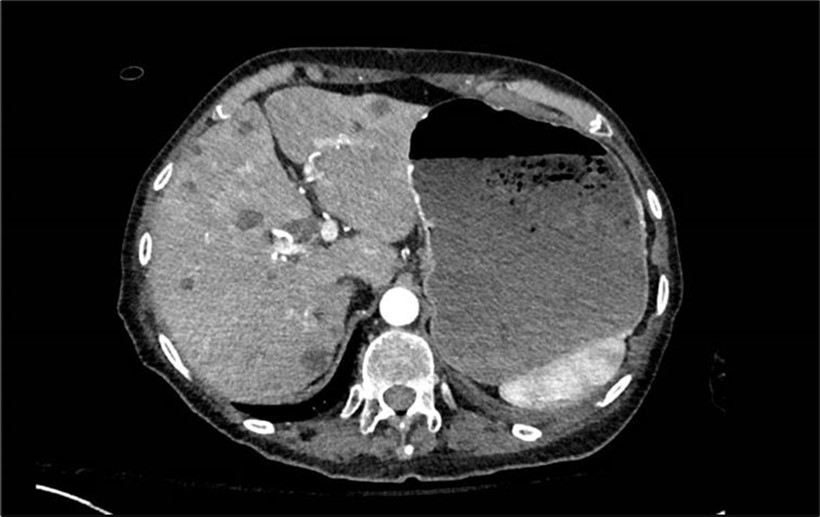

A right upper quadrant ultrasound showed a hypoechoic lesion in the head of the pancreas measuring 3.1 cm, associated with dilation of the main pancreatic and common bile duct. The liver appearance was heterogeneous with focal hypodense lesions. Further blood work was remarkable for a carcinoembryonic antigen of 2139 ng/mL and cancer antigen 19-9 was, 11782 U/mL. A CT chest, abdomen, and pelvis with contrast showed a 3.4x2.5 cm pancreatic head mass invading the duodenum, occlusive thrombi of the main portal vein and superior mesenteric vein, multiple liver lesions, and a distended stomach concerning for partial gastric outlet obstruction (Image 2). The diagnosis of pancreatic adenocarcinoma was confirmed via biopsy.

Image 2.CT scan showing liver with multiple metastatic lesions and a large stomach